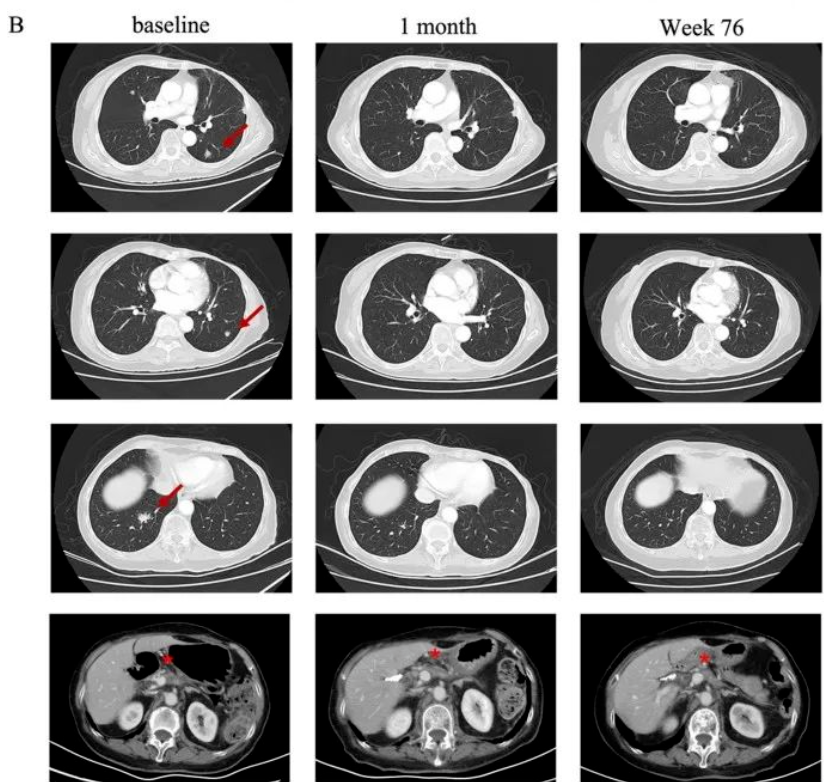

世界知名期刊《新英格兰医学杂志》,报道了1例75岁的转移性胰腺癌患者,经CT041细胞治疗后,靶病灶和转移灶明显缩小的案例。

该患者为pT2N0期的转移性胰腺癌(Claudin18.2表达为3+/60%),既往接受过手术、一线S-1单药化疗效果不佳,病情持续进展,且肺部出现转移灶。此时临床已无其他适合的治疗方法,抱着最后的希望,她在2021年7月,接受了CT041细胞回输治疗。

结果显示,在治疗后第4周,患者达到部分缓解(PR)。之后肺部靶病灶进一步消失,最终幸运的达到了完全缓解(CR)!截至末次随访(2023年7月)时,患者仍处于持续缓解状态。

图1 该患者肺部病变的放射学评估

▲图源J Hematol Oncol,版权归原作者所有,如无意中侵犯了知识产权,请联系我们删除

注:红色箭头表示目标病变;★表示原发病变。